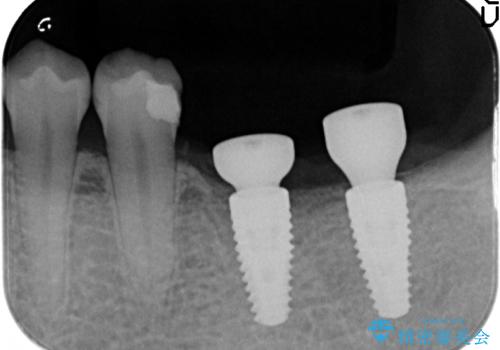

左下にインプラント(ストローマン)を2本埋入し、オールセラミッククラウンによる補綴を行いました。

ストローマンについて

当院では主にストローマンという種類のインプラントを治療に用いています。

ストローマンは世界的にもNo1のシェアを誇り、骨との適合にも優れたインプラントです。

カスタムアバットメントは患者様それぞれの歯茎に合わせて製作されたオーダーメイドのアバットメントです。

既製のアバットメントに比べ適合がよく、高い清掃性を誇ります。